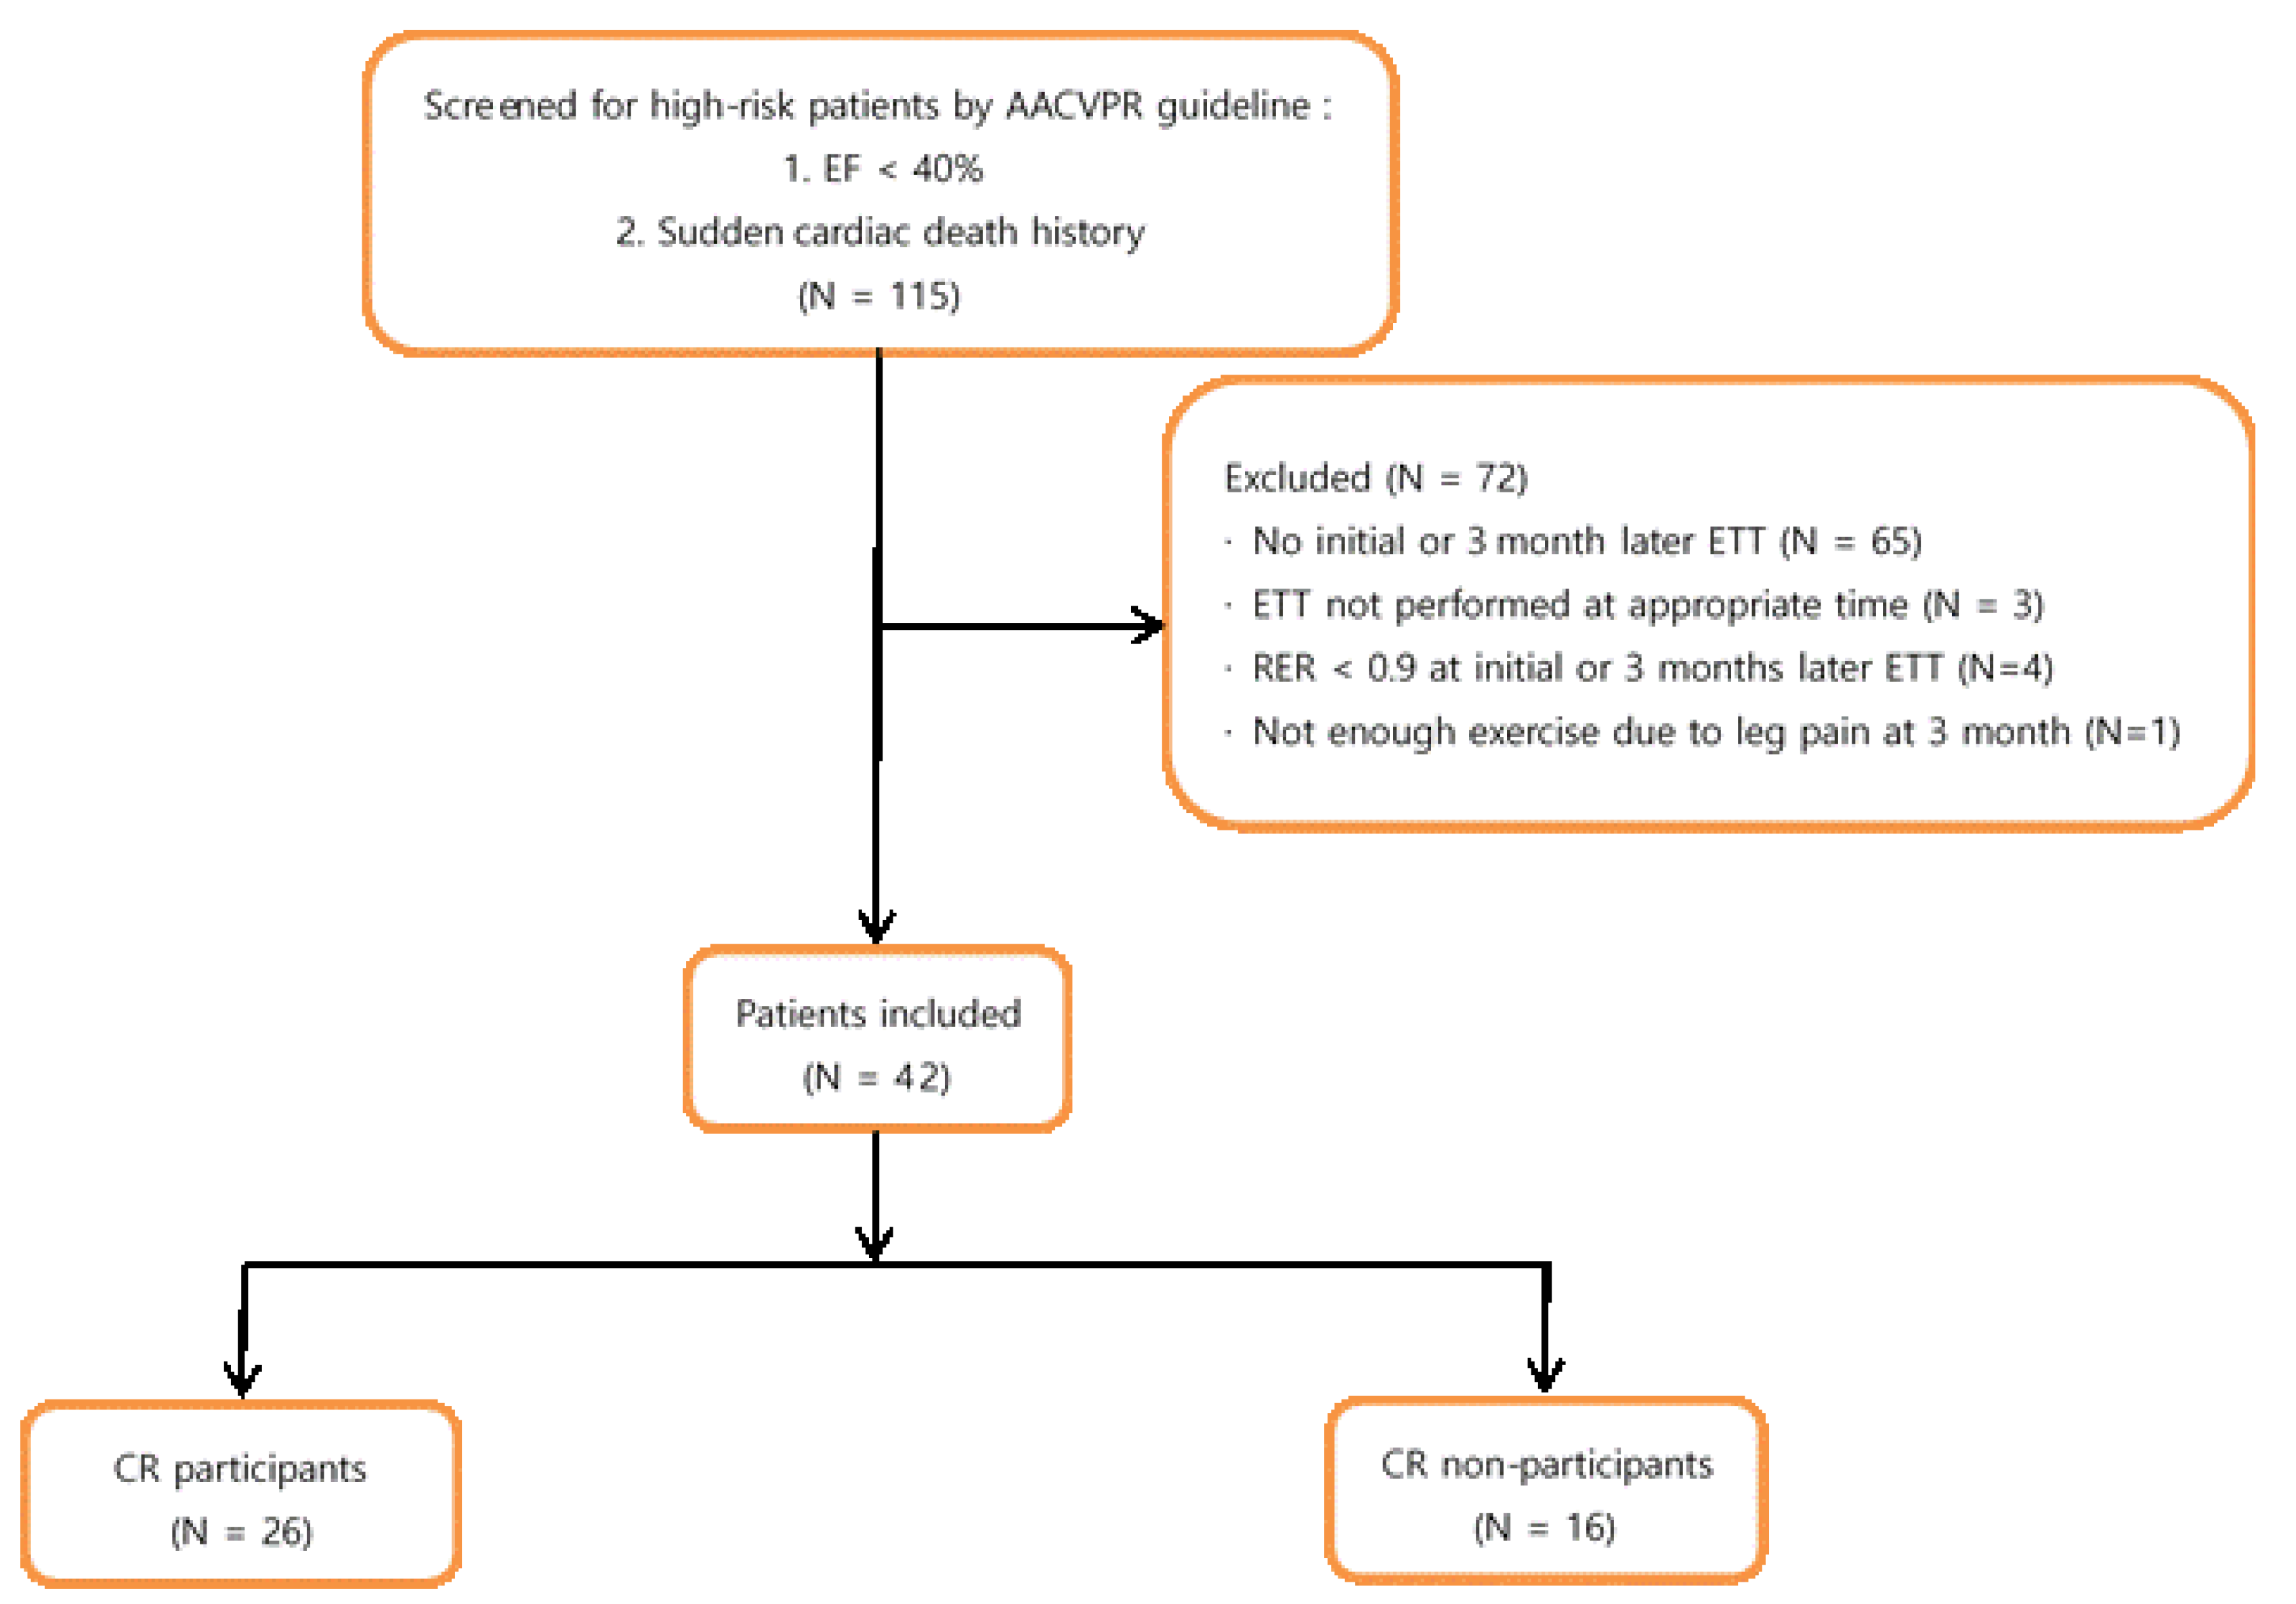

2.1. Subjects

- LVEF < 40%;

- A survivor of cardiac arrest or sudden death;